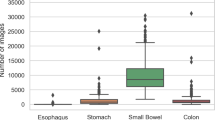

Berens, J., Mackiewicz, M. & Bell, D. Stomach, intestine, and colon tissue discriminators for wireless capsule endoscopy images. Proc. SPIE 5747, Medical Imaging Image Processing http://dx.doi.org/10.1117/12.594799.